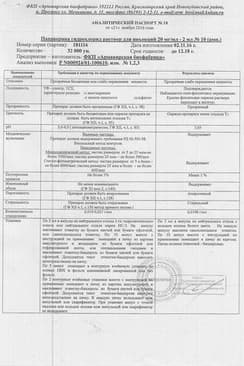

Инструкция по применению Папаверина гидрохлорид раствор 2% амп 2 мл N10

Состав препарата Папаверина гидрохлорид

Раствор для инъекций в виде прозрачной, слабоокрашенной жидкости.

1 мл

папаверина гидрохлорид 20 мг

Вспомогательные вещества: динатрия эдетат - 0.05 мг, метионин - 0.1 мг, вода д/и - до 1 мл.

2 мл - ампулы (5) - упаковки контурные ячейковые (1) - пачки картонные.

2 мл - ампулы (5) - треи картонные (1) - пачки картонные.

2 мл - ампулы (5) - упаковки контурные ячейковые (2) - пачки картонные.

2 мл - ампулы (5) - треи картонные (2) - пачки картонные.